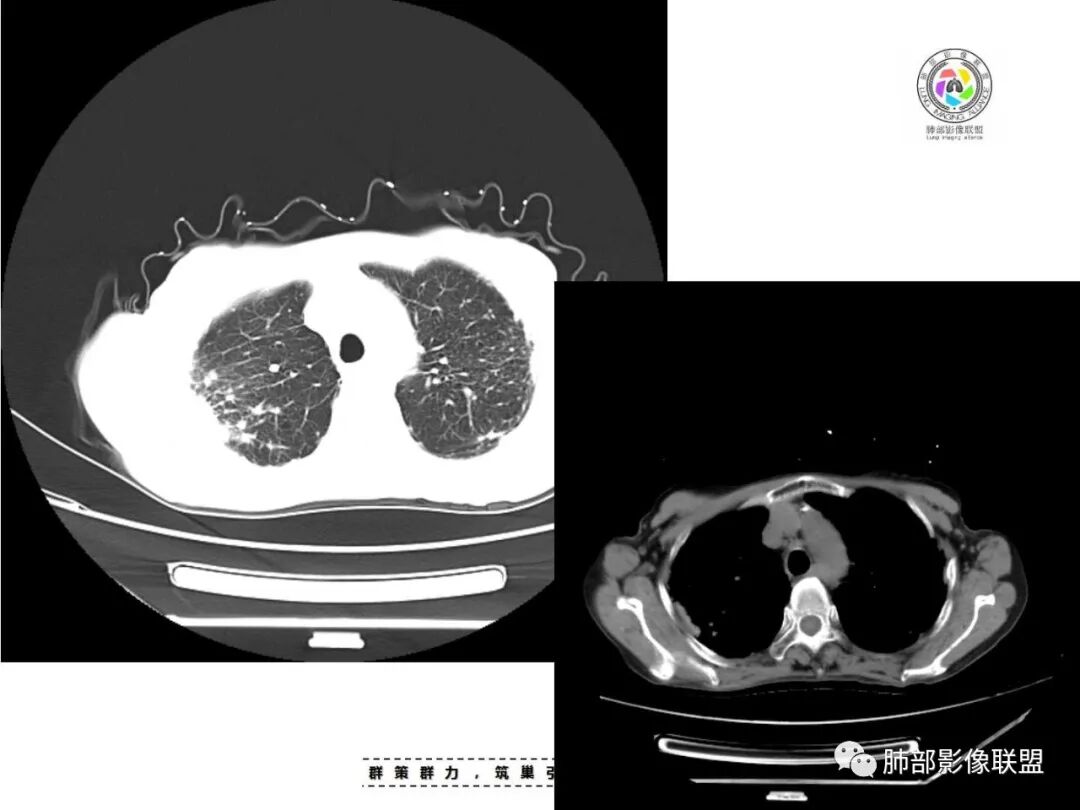

患者老年女性,亚急性起病,主要症状表现为咳嗽、咳痰半月余,查体:双现呼吸音粗,双肺可闻及痰鸣音。胸部CT:双上肺胸膜下可见多发小叶实变影,双上肺可见多发小叶中心性结节及小叶间隔增厚,右上肺后段可见亚段性实变影,内见多发空洞,前段可见GGO及树芽征,后段局部支气管闭塞,肺门淋巴结肿大并钙化。病灶整体:有气道、间质播散,一元论考虑肺结核合并支气管结核可能性大,建议好好查痰;这样病灶:明显实变+空洞+气道播散,若是结核,痰涂片找到抗酸杆菌应该没问题。建议支气管镜检查助诊,了解有无支气管结核及合并腺癌的可能。

1.双肺片状影、大小不等斑片影、结节影、树芽等,病灶密度偏高多钙化。

2.病灶上肺为主,胸膜下分布为主。双肺病灶明显不对称,右肺块状影较大。

3.纤维条索影广泛杂乱、牵拉,横向分布为主,这点给人也印象很深!

4.纵隔轻度右移。双肺门纵隔淋巴结增大钙化。

1.胸膜下为主,簇状分布,大小不等,新旧不等,树芽,密度偏高等等都结核病变影像学特点。

2.多数尘肺结节影相对比较随机,没有胸膜下分布优势。

尘肺结节显得“游离”、清晰,一般较为均匀,很少呈多形性、斑片、树芽或新旧不等改变,晚期形成的纤维块状影多是双上肺中带对称分布,也很少纵隔偏移。